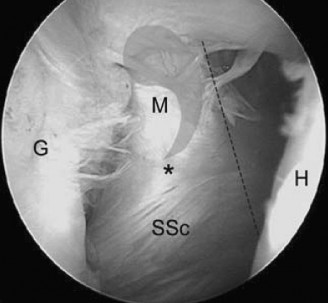

The correct answer is (A). When a chronic, retracted subscapularis tendon tear is present, the superolateral border of the tear can be identified by a comma-shaped ligamentous structure that exists at this border. This is composed of an avulsed superior glenohumeral ligament blending with the coracohumeral ligament and is called the comma sign (see Fig. 2–12).

_Figure 2–12_Comma sign, indicating the superior border of a chronic, retracted subscapularis tendon tear. G, glenoid; H, humerus; SSc, subscapularis; M, medial sling of biceps (comma); , junction of medial sling of biceps and subscapularis tendon. (Redrawn from Burkhart SS, Lo IKY. Arthroscopic rotator cuff repair. J Am Acad Orthop Surg. 2006;14(6):333–346.)